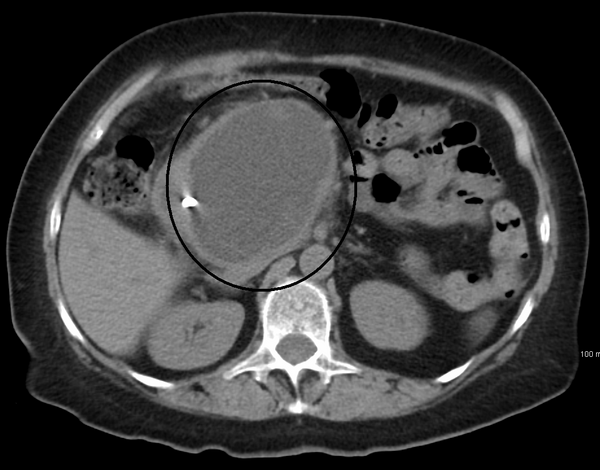

Локализация эхинококковой кисты в поджелудочной железе (с комментарием)

Локализация эхинококковых кист в поджелудочной железе относится к редким формам заболевания и встречается у 0,1—0,21% больных [1, 2]. Как правило, при такой локализации паразитарные кисты одновременно выявляют в других органах — печени, легких, селезенке и пр. [2].

В нашей клинике находился на лечении больной, у которого была выявлена киста только в поджелудочной железе. Приводим это наблюдение.

Больной Э., 41 года, госпитализирован в отделение хирургии № 1 Республиканской больницы № 2 Махачкалы 11.03.14 с жалобами на схваткообразные боли в животе, вздутие живота, тошноту, рвоту. В 2002 г. перенес холецистэктомию.

При обзорной рентгенографии органов брюшной полости отмечена пневматизация толстой кишки, слева на уровне XII ребра округлая тень с четкими контурами размером 4×4 см (рис. 1).

По данным экскреторной урографии, чашечно-лоханочная система не изменена, имеется забрюшинная киста вне почки.

УЗИ: печень увеличена на 3 см за счет левой доли, структура диффузно неоднородная; диаметр общего желчного протока 7 мм; селезенка не увеличена, диаметр селезеночной вены 10 мм; кистозные образования в брюшной полости и забрюшинном пространстве не выявлены.

При госпитализации диагностирована острая спаечная кишечная непроходимость, назначено консервативное лечение. Непроходимость разрешена в течение 1-х суток.

18.03 больной оперирован по поводу кисты брюшной полости. В области хвоста поджелудочной железы выявлено округое плотное опухолевидное образование размером 4×4 см, спаянное с селезеночными артерией и веной.

Макропрепарат (рис. 3): киста поджелудочной железы размером 4×4 см, в полости густой гной сероватого цвета без запаха, стенки полости кальцинированы.

Результаты морфологического исследования: эхинококковая киста с участками обызвествления хитиновой оболочки.

Заключительный диагноз: эхинококковая киста поджелудочной железы, брюшинные спайки.

Послеоперационное течение без осложнений. Пациент выписан из клиники на 10-е сутки.

В этом наблюдении представляет интерес не только редкая локализация эхинококковой кисты, но и отсутствие паразитарных кист в других органах (печени, легких).

Представлен редкий случай локализации эхинококковой кисты в поджелудочной железе.

При таком варианте расположения эхинококковой кисты показан органосохраняющий вариант операции — дистальная резекция поджелудочной железы с сохранением селезенки (в специализированной клинике — срединная резекция поджелудочной железы). Оптимальным явился бы лапароскопический способ выполнения операции. Независимо от объема и способа выполнения операции следовало соблюдать эпидемические профилактические меры (аспирация содержимого кисты с последующим введением в ее просвет гипертонического раствора хлористого натрия и обкладывание операционного поля салфетками с тем же раствором. Утверждение авторов о том, что у больного единственная эхинококковая киста требует дополнительного исследования — КТ или МРТ с прицельным изучением печени. Выполненное перед операцией УЗИ, при котором не была диагностирована киста поджелудочной железы, не может служить критерием для исключения эхинококкового поражения печени.